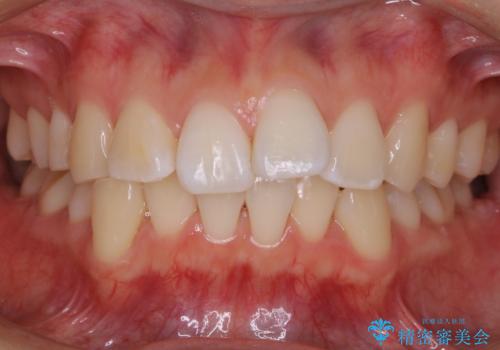

【再矯正】後戻りによるガタつきをマウスピースで改善!

- 以前、中学生から高校生にかけてワイヤー装置による抜歯矯正を経験されている患者さんで、大人になってからのライフスタイルの変化でリテーナーを継続使用することができず、ガタつきが目立つようになってきてしまったのでもう一度矯正治療がしたいという主訴でご来院されました。

既に上下左右の4番目の歯が抜歯されているため、今回の治療では抜歯をせず歯の移動だけでガタつきを治す必要があり難易度が高くなっていました。